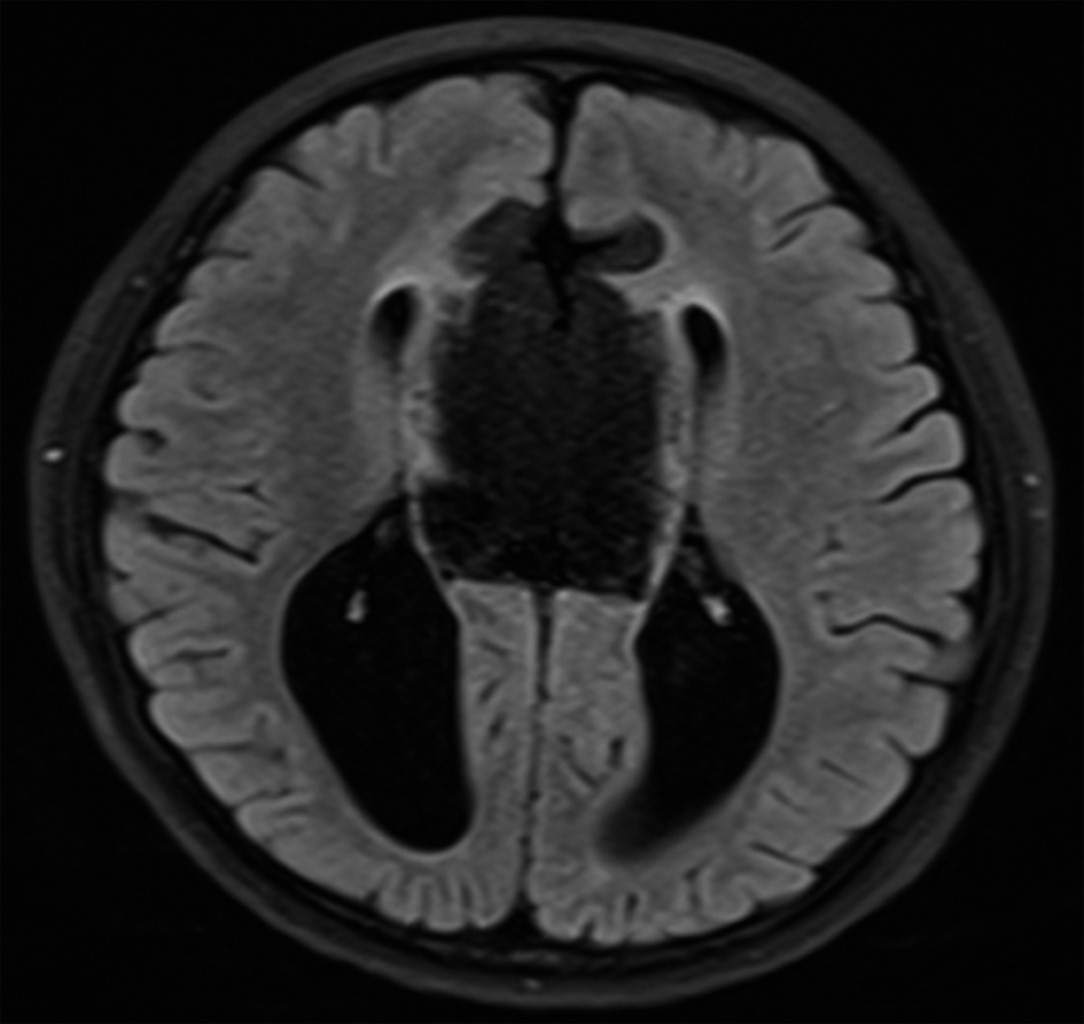

Masculino de siete años edad con antecedente de cefalea, muestra deficiencias en la coordinación motora, equilibrio y lenguaje expresivo. Acude a consulta en medio institucional, donde médico tratante solicita como estudio de abordaje inicial resonancia magnética de encéfalo, en la que se observan cuernos frontales pequeños con dilatación de los trígonos y cuernos occipitales identificando los signos radiológicos en cortes axiales "carro de carreras" (Figura 1) y en cortes coronales "cabeza de alce" (Figura 2). Lo antes descrito se relaciona con disgenesia del cuerpo calloso, la cual se corrobora en cortes sagitales donde no se identifica en la línea media el cuerpo calloso. Además, se identifica masa ubicada en topografía pericallosa de localización anterior, centrada hacia la fisura interhemisférica, lesión de forma irregular de comportamiento hiperintenso en T1 (Figura 1) y T2 (Figura 2), que suprime en secuencia de supresión grasa (Figura 3) y que mide aproximadamente 2.4 × 3.4 × 5.4 cm de diámetro máximo en sus ejes laterolateral, cefalocaudal y rostroventral, respectivamente.

El estudio de elección es la resonancia magnética simple que realiza secuencias para valorar la supresión de la grasa, y la secuencia ecogradiente o T2 que nos ayuda a valorar calcios periféricos, ya que en esta secuencia se visualiza el artefacto blackdots en la presencia de calcificaciones. La espectroscopia con tiempo de eco corto nos ayuda a valorar los metabolitos como la grasa y también la espectroscopia con tiempo de eco largo nos ayuda a valorar si la masa presenta un patrón tumoral.1,4

Figura 3